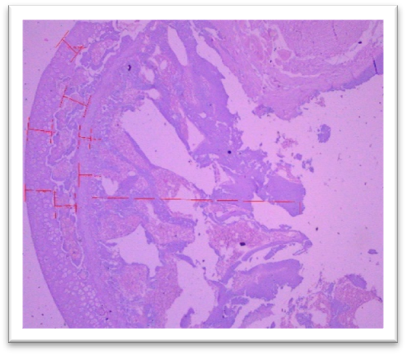

Histopathology

On day 42, rats were sacrificed for histopathological examination. Group I (Normal) and Group II (Lanthanum Carbonate only) showed normal kidney and liver architecture. Group III (Chronic Kidney Disease control) exhibited kidney damage, including crystals, congestion, haemorrhage, interstitial nephritis, and tubular dilatation. Group IV (Lanthanum Carbonate @150 mg/kg) showed moderate kidney fibrosis, mononuclear infiltration, and crystals. Group V (Lanthanum Carbonate @250 mg/kg) had mild fibrosis and sparse crystals. Group VI (Lanthanum Carbonate @500 mg/kg) showed minimal fibrosis and negligible crystals. Group VII (Lanthanum Carbonate @750 mg/kg) had minimal lesions with no crystals. Liver sections were normal in all groups. Histopathology studies revealed , The kidneys from a Chronic Kidney Disease (CKD) control rat (Group III) displayed significant macroscopic changes, including an increase in overall kidney size and the presence of multifocal, pinpoint, white granular raised lesions that were widely dispersed across the cortical surface. These observations are consistent with pathological alterations associated with CKD. Similar findings were reported by Yang et al. (2013) and Ali et al. (2015), who observed renal tissues exhibiting varying degrees of swelling and the presence of widespread white granular deposits on the cortical surfaces, consistent with the pathological features described in this study. Damment et al. (2011) observed significant changes in kidney architecture of Adenine induced Chronic Kidney Disease animals. The kidney from Group VII, treated with Lanthanum Carbonate @ 150mg/kg, 250mg/kg , 500mg/kg and 750 mg/kg body weight, demonstrated significant architectural improvement, along with a notable reduction in the number of crystalline deposits, indicating a substantial restoration of renal morphology and potential therapeutic efficacy at this dosage.

Fig. 19 Group III Kidney exhibits the crystals, congestion and haemorrhage. interstitial infiltration of mononuclear cells and fibrosis. Dilatation of the tubules, focal oedema, and focal interstitial nephritis under H & E 400X.

Fig. 20 Group IV Kidney shows moderate focal mononuclear cell infiltration with moderate fibrosis, and 3- 4 crystals under H & E 400 X

Fig. 21 Group V Kidney exhibits mild and focal interstitial fibrosis, sparse mononuclear cell infiltration, mild tubular dilatation, and 1- 2 crystals under H & E 400X.